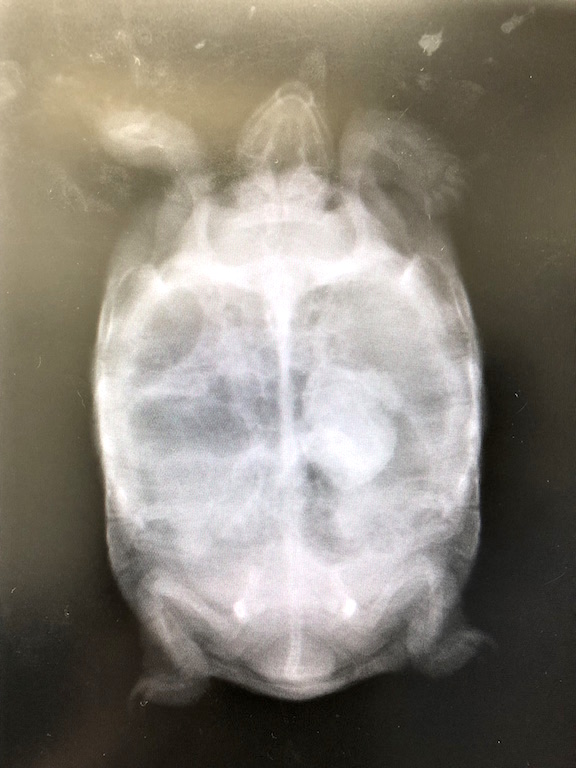

タイガーの結石を疑った私は、すぐに近所の動物病院でレントゲン撮影をして頂きました。

この病院は犬猫専門なのですが、日頃から抱卵や結石・肺炎などが気になった際にレントゲンのみをお願いしています。

悪い予感は的中しました。

胸のあたりに石らしき物体が写り込んでいます。

現在のタイガーは甲長10cm/体重220g、奇しくも当時の2号と同じサイズです。